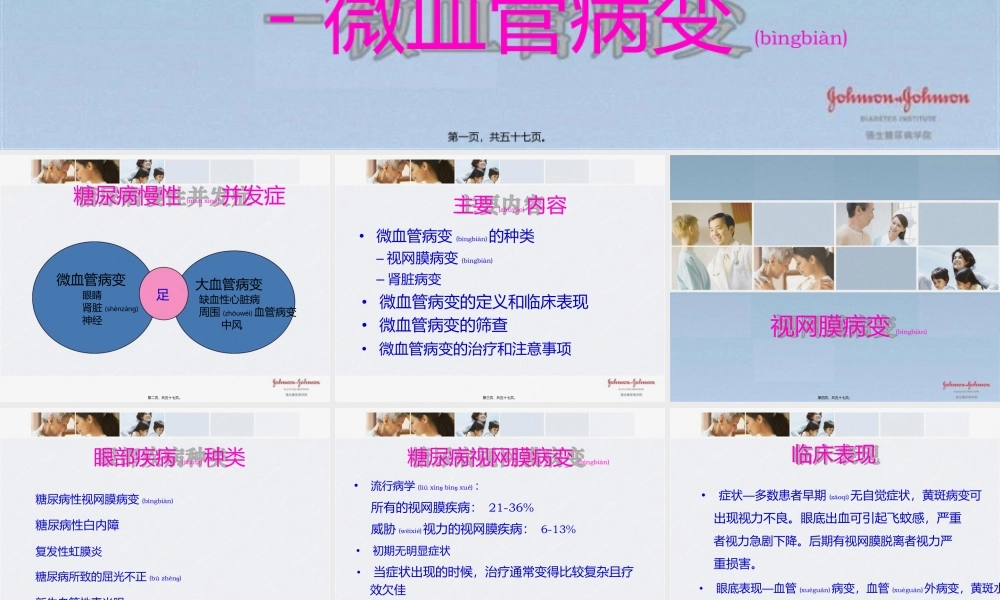

糖尿病慢性(mànxìng)并发症-微血管病变(bìngbiàn)第一页,共五十七页。糖尿病慢性(mànxìng)并发症微血管病变眼睛肾脏(shènzàng)神经大血管病变缺血性心脏病周围(zhōuwéi)血管病变中风足第二页,共五十七页。主要(zhǔyào)内容•微血管病变(bìngbiàn)的种类–视网膜病变(bìngbiàn)–肾脏病变•微血管病变的定义和临床表现•微血管病变的筛查•微血管病变的治疗和注意事项第三页,共五十七页。视网膜病变(bìngbiàn)第四页,共五十七页。眼部疾病(jíbìng)种类糖尿病性视网膜病变(bìngbiàn)糖尿病性白内障复发性虹膜炎糖尿病所致的屈光不正(bùzhènɡ)新生血管性青光眼第五页,共五十七页。糖尿病视网膜病变(bìngbiàn)•流行病学(liúxínɡbìnɡxué):所有的视网膜疾病:21-36%威胁(wēixié)视力的视网膜疾病:6-13%•初期无明显症状•当症状出现的时候,治疗通常变得比较复杂且疗效欠佳•视网膜病变的筛查非常重要第六页,共五十七页。临床表现•—症状多数患者早期(zǎoqī)无自觉症状,黄斑病变可出现视力不良。眼底出血可引起飞蚊感,严重者视力急剧下降。后期有视网膜脱离者视力严重损害。•—眼底表现血管(xuèguǎn)病变,血管(xuèguǎn)外病变,黄斑水和增殖性病变(bìngbiàn)。第七页,共五十七页。病变严重程度散瞳眼底检查所见无明显视网膜病变无异常非增殖期(NPDR)轻度非增殖期仅有微动脉瘤中度非增殖期微动脉瘤,存在轻于重度NPDR的表现重度非增殖期出现下列任何一个改变,但无PDR表现1.任一象限中有多于20处视网膜内出血2.在两个以上象限有静脉串珠样改变3.在一个以上象限有显著的视网膜内微血管异常增殖期(PDR)出现以下一种或多种改变:新生血管形成、玻璃体积血或视网膜前出血视网膜病变(bìngbiàn)和失明糖尿病性视网膜病变的国际(guójì)临床分级标准第八页,共五十七页。病变严重程度眼底检查所见无明显糖尿病性黄斑水肿后极部无明显视网膜增厚或硬性渗出有明显糖尿病性黄斑水肿后极部有明显视网膜增厚或硬性渗出轻度后极部存在部分视网膜增厚或硬性渗出,但远离黄斑中心中度视网膜增厚或硬性渗出接近黄斑但未涉及黄斑中心重度视网膜增厚或硬性渗出涉及黄斑中心糖尿病性黄斑水肿(shuǐzhǒng)分级第九页,共五十七页。我国采用的分期标准(biāozhǔn)糖尿病视网膜病变的分期期别眼病检查(jiǎnchá)所见(+)(++)(+)(++)(+)(++)较小,易数较多,不易(bùyì)数较小,易数较多,不易数...